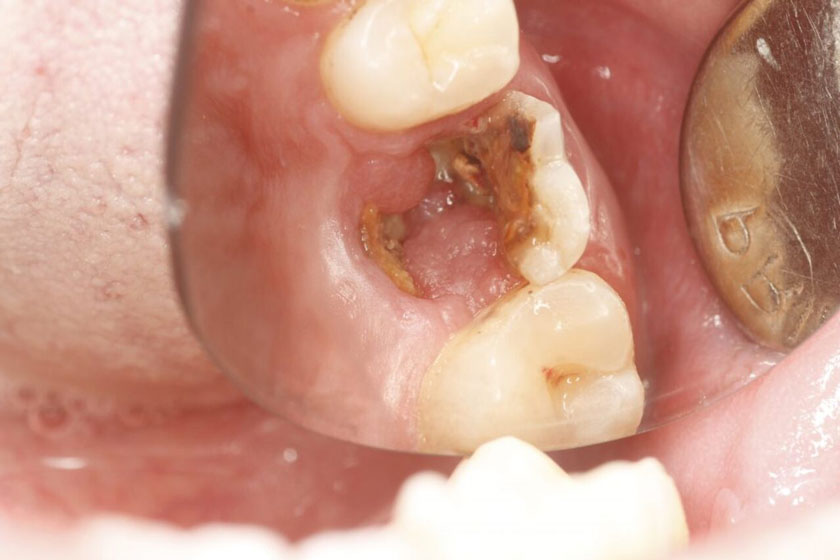

Biến chứng của sâu răng mức độ nặng

Sâu răng nếu không điều trị sẽ để lại biến chứng nguy hiểm. Khi vi khuẩn tấn công men răng, ngà răng và xâm nhập tủy răng sẽ gây ra tình trạng viêm tủy răng. Nếu viêm tủy kéo dài, sẽ dẫn đến viêm mô tế bào, áp-xe răng, phá hủy cấu trúc mô và xương quanh răng, làm hàm và lợi sưng to, đau nhức dữ dội.

Sâu răng nặng có thể làm sưng hàm, đau nướu, khó há miệng